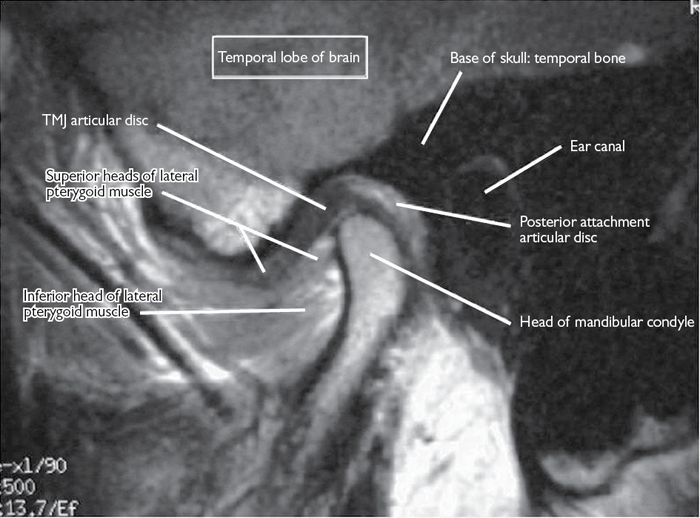

MR Imaging of Temporomandibular Joint Dysfunction A Pictorial Review

Temporomandibular Joint Anatomy MRI TMJs Anatomy Free Sagittal Tmj Open Mouth Mri Describe the normal ultrasound, ct, and mri appearances of tmj; The temporomandibular joint (tmj) is an atypical synovial joint located between the condylar process of the mandible and the mandibular. Acute findings include an effusion, synovial enhancement and thickening, enhancing erosions, and bone marrow oedema ( fig 8 a). In order to perform the open mouth scans, a bite block. Tmj Open Mouth Mri.